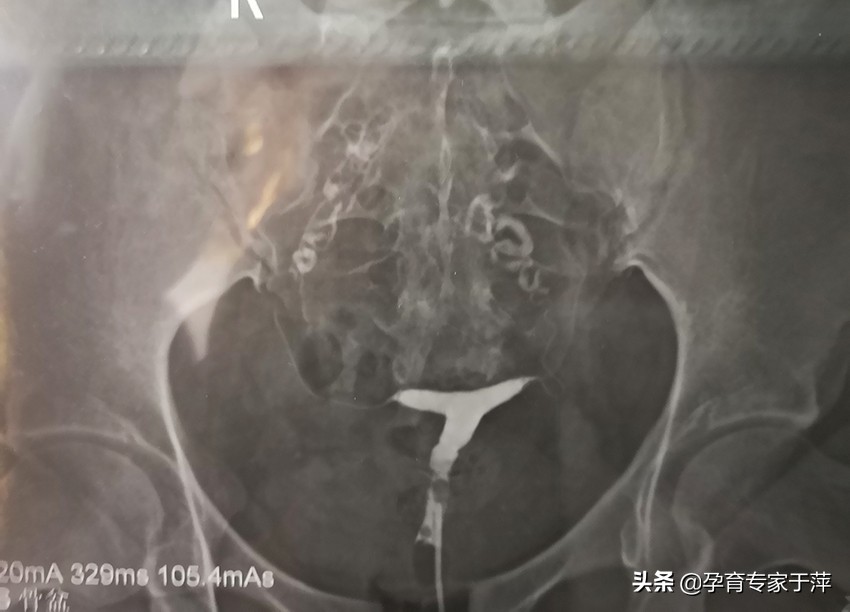

2、输卵管不通

显示一侧或双侧输卵管不显影或部分显影,盆腔没有造影剂涂抹。如果盆腔有造影剂涂抹,说明至少一侧输卵管是通的。